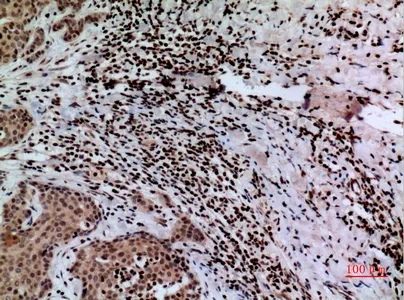

FOXP1 Rabbit Polyclonal Antibody

Cat: APRab11113

Size1:50μl Price1:$118

Size2:100μl Price2:$220

Size3:500μl Price3:$980